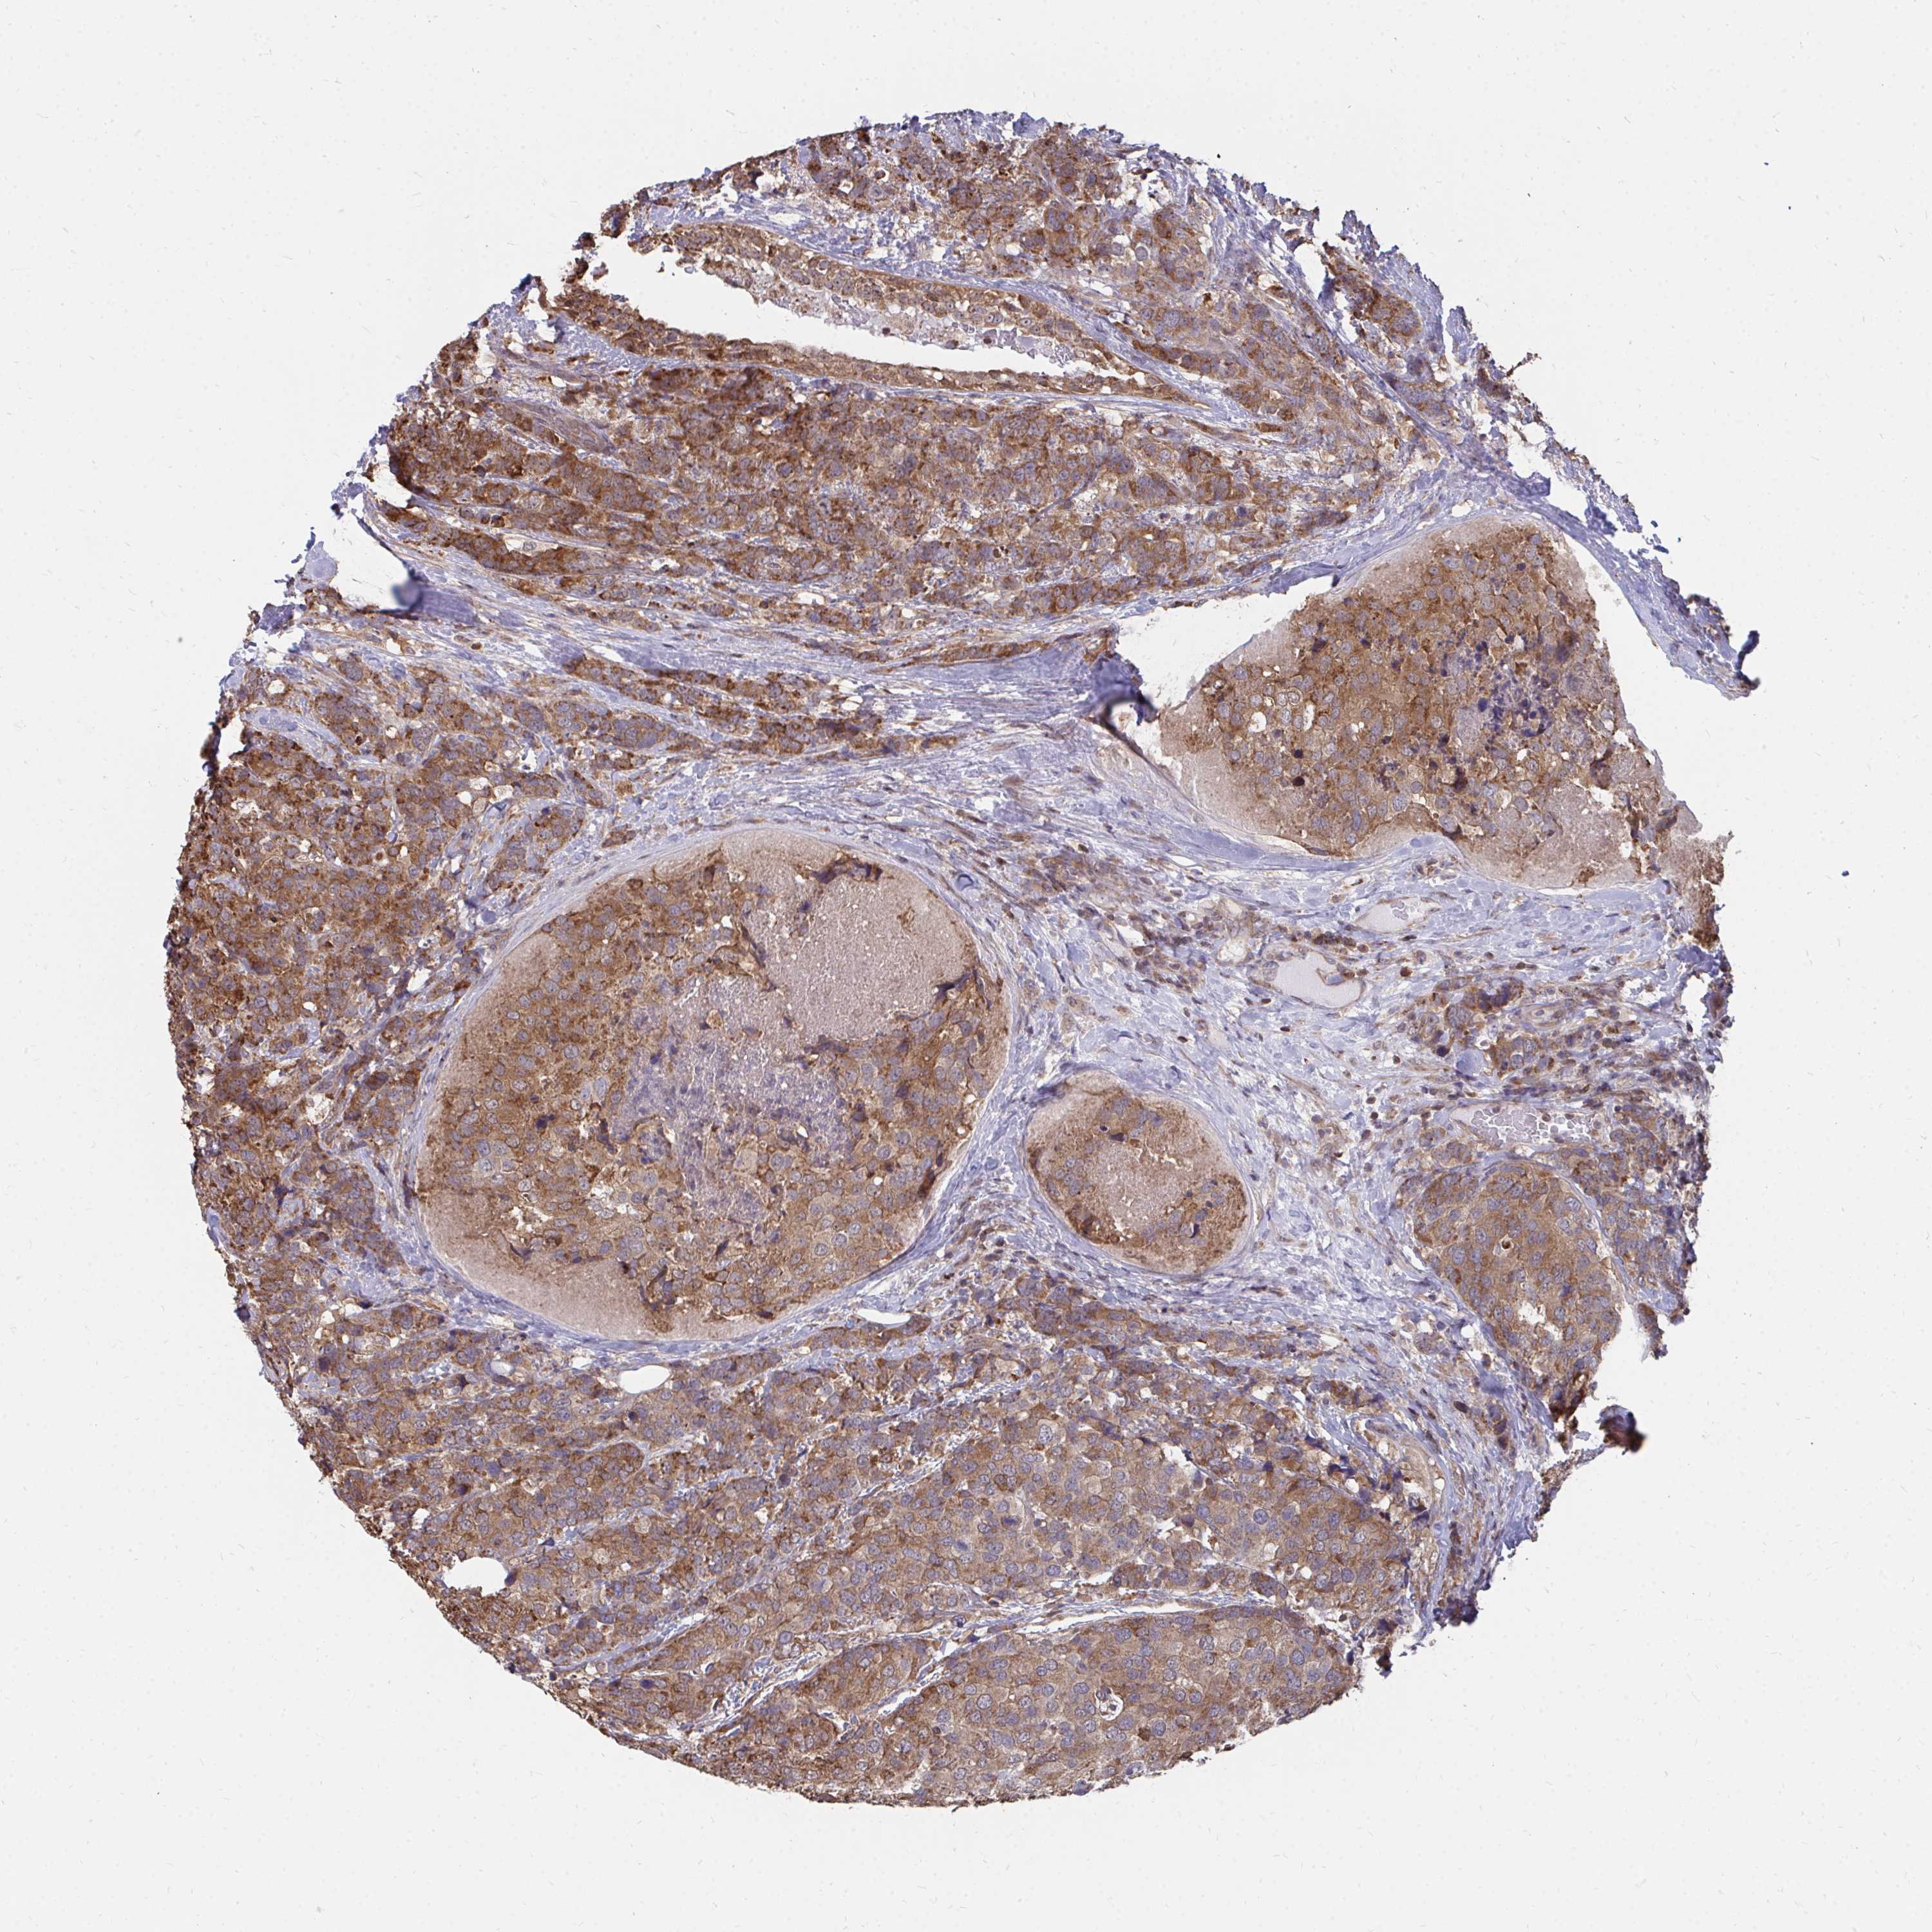

CANCER BREAST CANCER Show tissue menu

Breast cancer

Human cancer